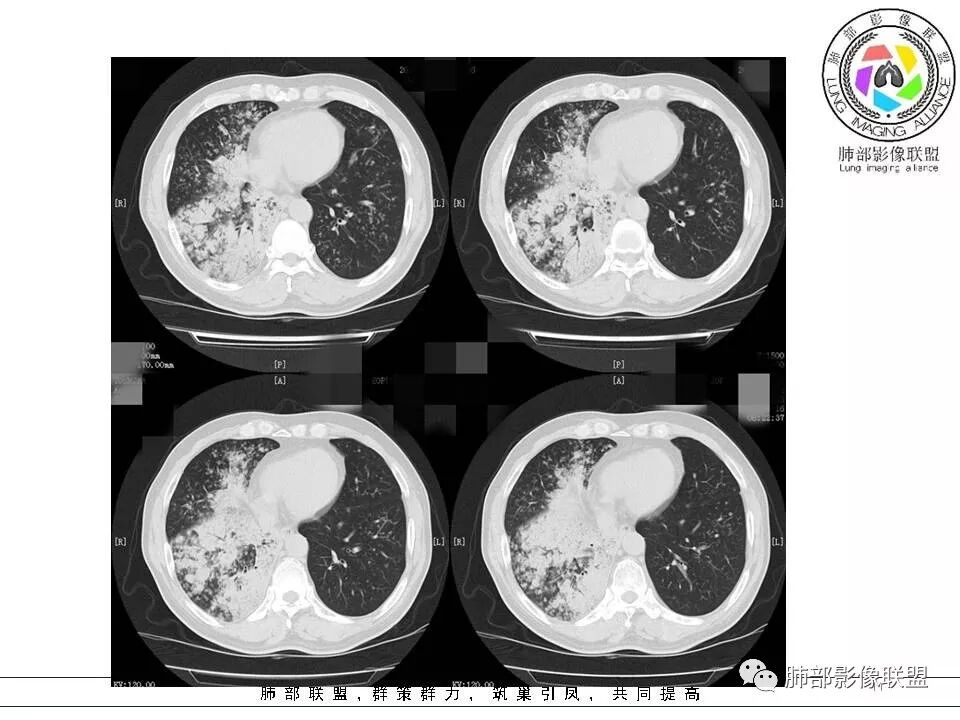

病灶的形态与分布如何?

多发实变影,呈叶段分布,形态及密度都比较单一,比较柔和

病灶的走形如何?                                                                                                以外围胸膜下分布为主,长轴与胸膜平行

病灶的边缘如何:

大部分边缘膨隆,局部边缘稍收缩

病灶内的支气管如何:                                                                            支气管走形通畅自然,部分于近端堵塞,管壁光整

病灶内的坏死如何?:                                                                                             病灶内有坏死空洞,大部分空洞内壁光整,部分空洞内少许分隔影,呈“鬼脸”样空洞

周围情况如何?:                                                                                                   周围肺野有模糊晕,未见明显树芽征,与胸膜有糊墙改变

患者临床轻影像重,CRP增高,社区获得性肺炎常规不考虑,年轻人,不是许多机会性感染的易感人群,特殊性感染性病变有结核和隐球,但是结核形态多发,好发于上叶及下叶背段,密度不均一,通常有树芽,而且结核空洞呈虫蚀样且内壁光整,不作为首先考虑病灶形态单一,有晕征,有空洞及空洞内分隔,病灶分布与胸膜平行,隐球比较符合,但是结核影像多样化,年轻人,也需要临床进一步检查除外结核。    病例为什么不首先考虑OP或淋巴瘤,病灶内支气管情况有助于判别,OP收缩性往往很强,所以病灶内支气管应该稍扩张而且没有堵塞,淋巴瘤起源于支气管粘膜下和肺间质,往往沿血管支气管束方向分布,与胸膜垂直为主,病灶内支气管壁增厚并直达远段,易合并支气管扩张;年轻人肺炎型肺癌少见,而且影像表现也不支持,如果患者治疗效果不好,需要临床进一步检查排查肺癌。